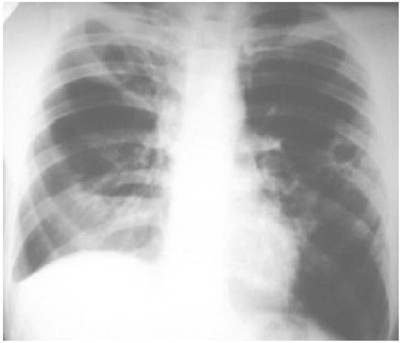

Это вид туберкулеза, при котором в легких на месте разрушенной ткани образуются полости. Заболевание может возникать при наличии другой формы туберкулеза легких, в основном - инфильтративной.